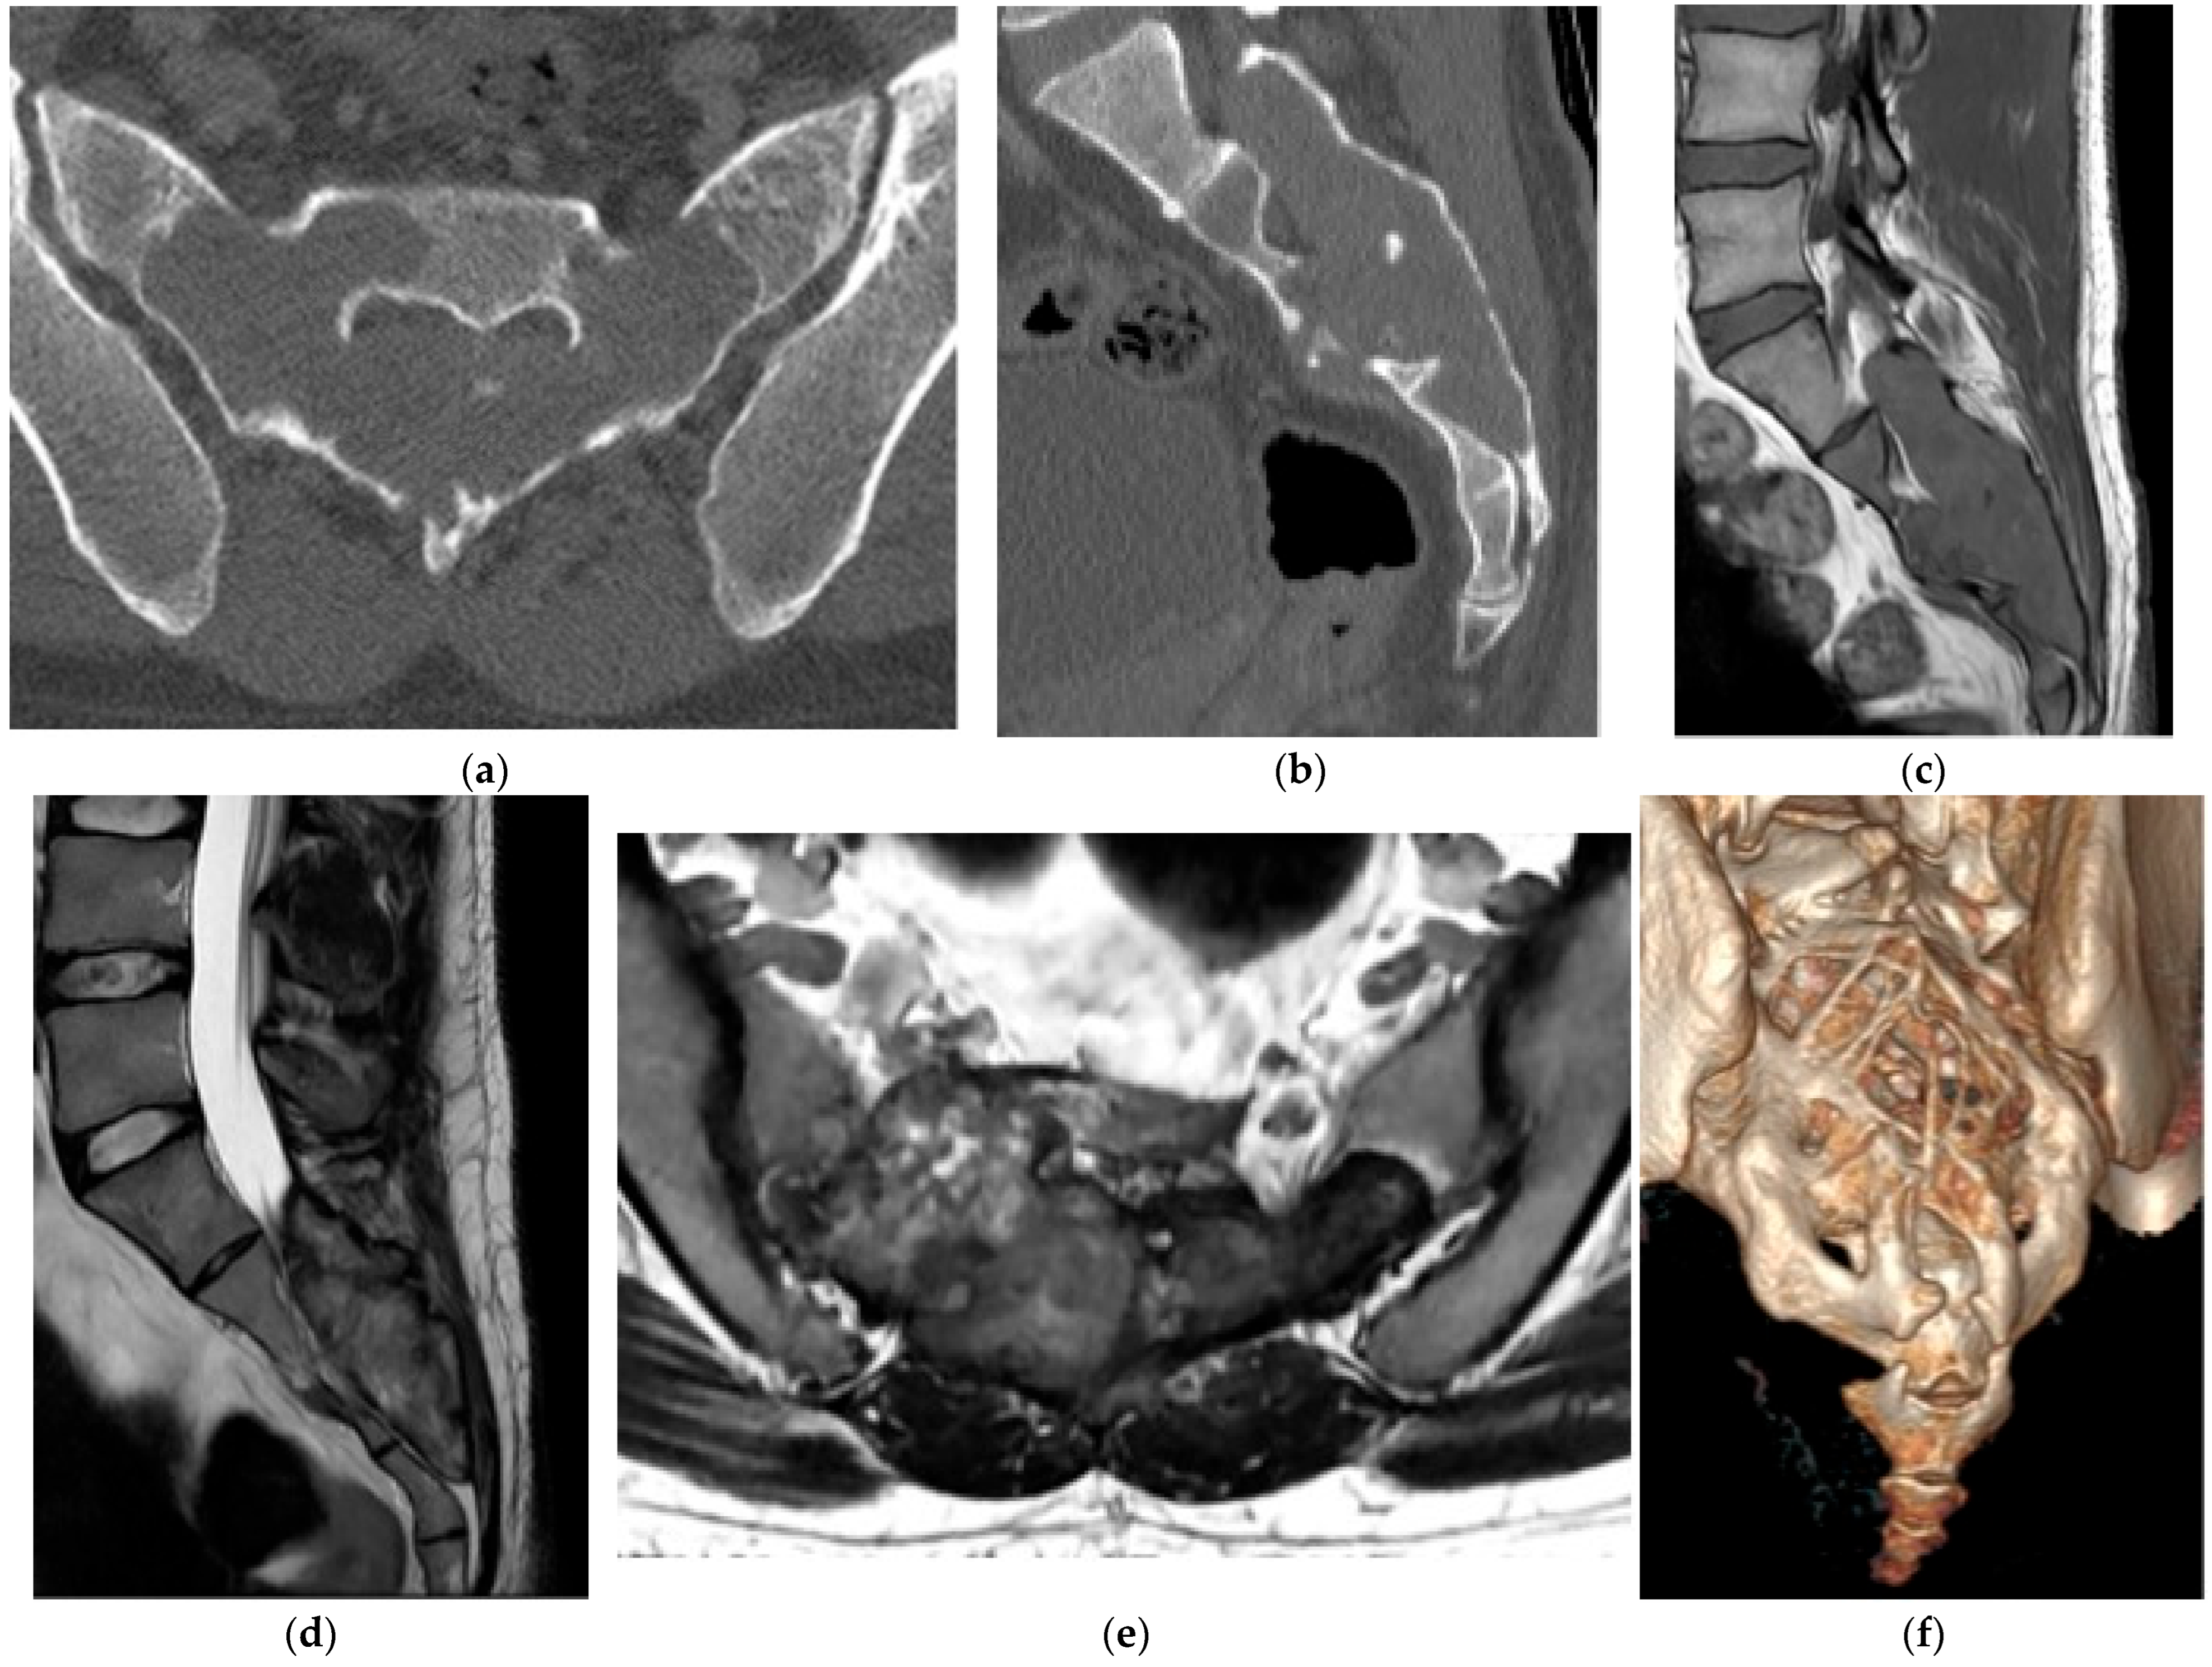

Giant Cell Tumor

2.3.2. Chordoma